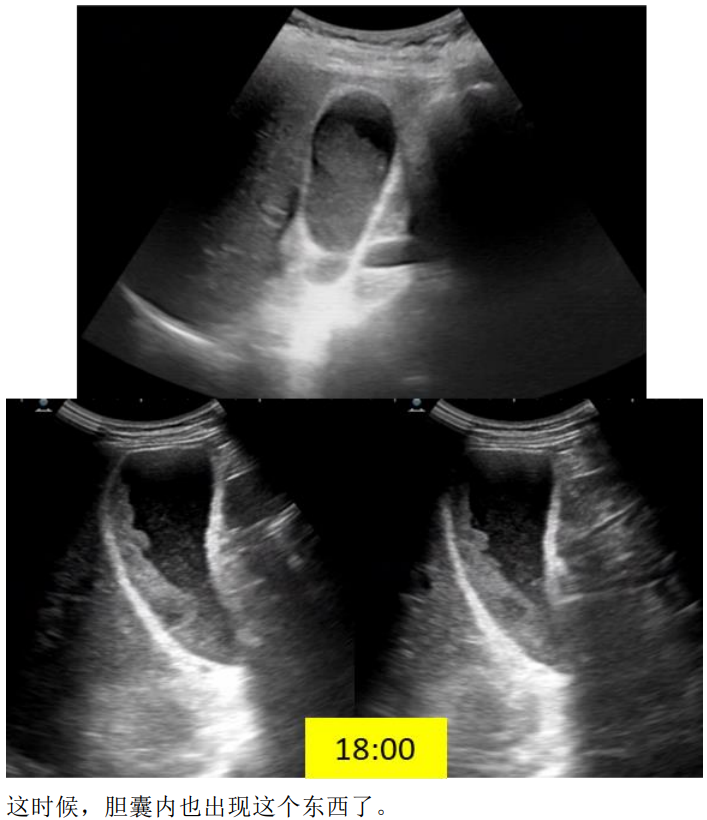

余留森 广东省中山市人民医院南朗分院 病史:女,72岁,上腹部疼痛2天 一、早晨8点,超声检查

DWI胆囊内病变呈高信号,ADC值下降,提示弥散受限。 LAVA-FLEX四像图:水像病变呈等低信号,脂肪像低信号,同反相位未见显著信号改变,提示病变不含大量脂肪成分。 小朋友,你是否也有很多问号? 超声,CT都提示胆囊未见异常。 MR发现胆囊里面这么大一坨东西。 它是什么,它来自哪里,它会去向何方? 没有伪影的MR是不正常的,机器问题,参数问题? 四、晚上18点,超声复查

五:胆泥 胆泥是胆汁中的为微观沉淀物,由黏蛋白、胆固醇晶体、胆红素钙盐和其他钙盐组成,可随体位变化移动,超声胆泥后方无明显声影。